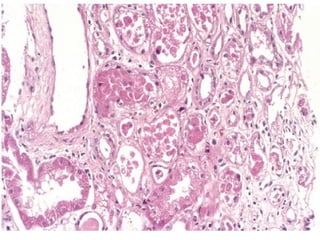

MCIROSCOPY

• Tubules - Atrophy in some and Dilation & Hypertrophy in others.

• Dilated tubules filled with colloid casts – THYROIDIZATON.

• Neutrophils in tubules - if acute reinfection occurs

• Chronic Interstitial Inflammation - cortex and medulla.

• It is not uncommon to see lymphocytes accompany just about

any chronic renal disease: glomerulonephritis, nephrosclerosis,

pyelonephritis. However, the plasma cells are most

characteristic for chronic pyelonephritis.

• Fibrosis - Around calyceal mucosa.

MCIROSCOPY • Tubules -Atrophy in some and Dilation & Hypertrophy in others. • Dilated tubules filled with colloid casts – THYROIDIZATON. • Neutrophils in tubules - if acute reinfection occurs • Chronic Interstitial Inflammation - cortex and medulla. • It is not uncommon to see lymphocytes accompany just about any chronic renal disease: glomerulonephritis, nephrosclerosis, pyelonephritis. However, the plasma cells are most characteristic for chronic pyelonephritis. • Fibrosis - Around calyceal mucosa.

• #20 “THYROIDIZATION” is another common hallmark of chronic pyelonephritis. To my knowledge, this is one of 3 things which look like thyroid, but are not. What are the other two? 1) Pars intermedia of pituitary 2) lactation breast lobule